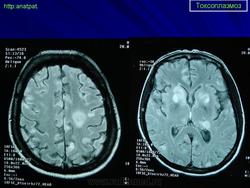

Церебральный токсоплазмоз.

Церебральный токсоплазмоз

Neurotoxoplasmosis